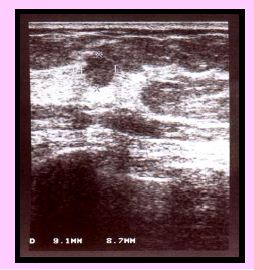

Nehmatné

RA: 0

HRT: 0